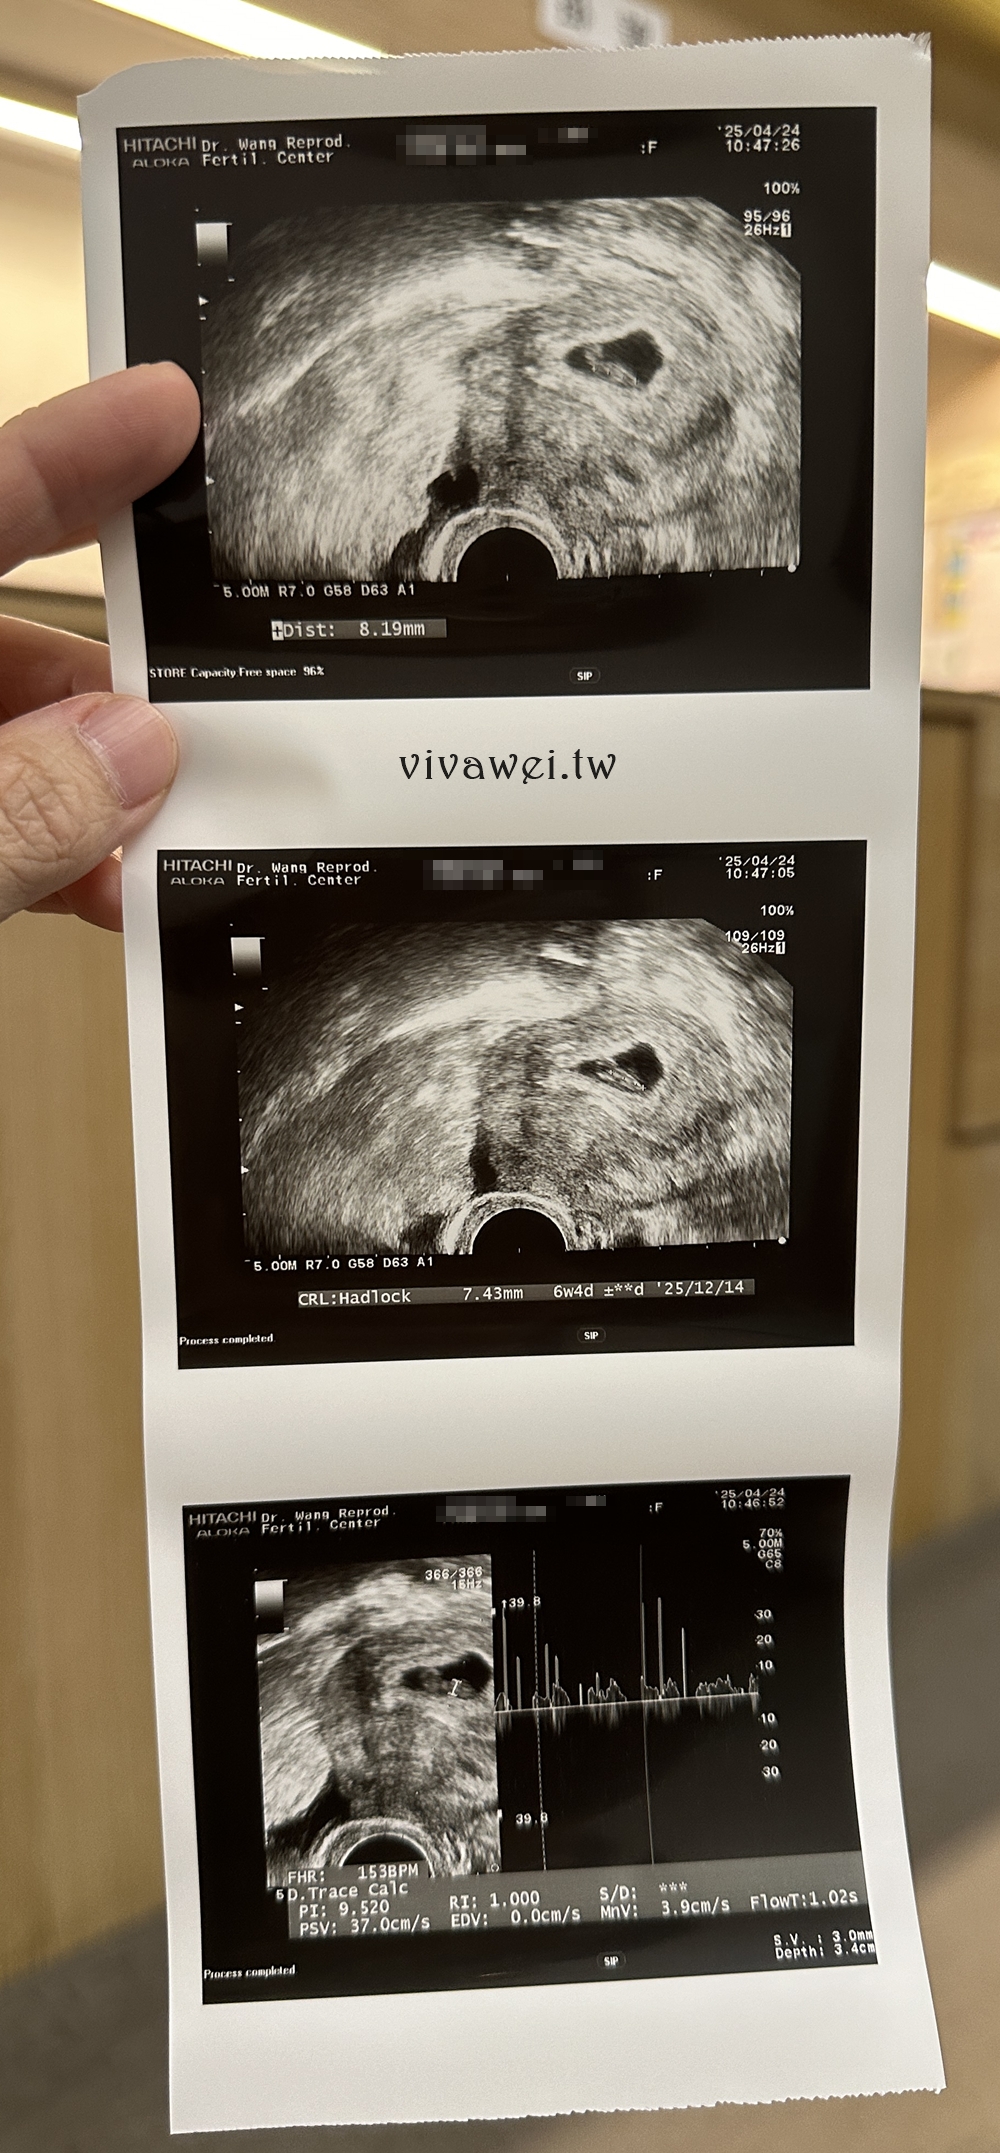

▲驗孕成功後我就沒特別約王醫師的門診了,因為王醫師的診都需要等好久,如果是約別的醫生就可以在指定的時間看診,對我來說比較方便!所以這天和診所約了11:00盧醫師的診,這天照了陰道超音波聽到小孩的心跳了,醫生還有拍了幾張超音波圖給我!

這天看診跟醫師反應近期覺得噁心和孕吐嚴重,所以醫生就開了止吐藥給我👌不然我這一胎大概從第五週吐到第二十二週,而且都是噴泉式孕吐,真的有夠慘啦😭